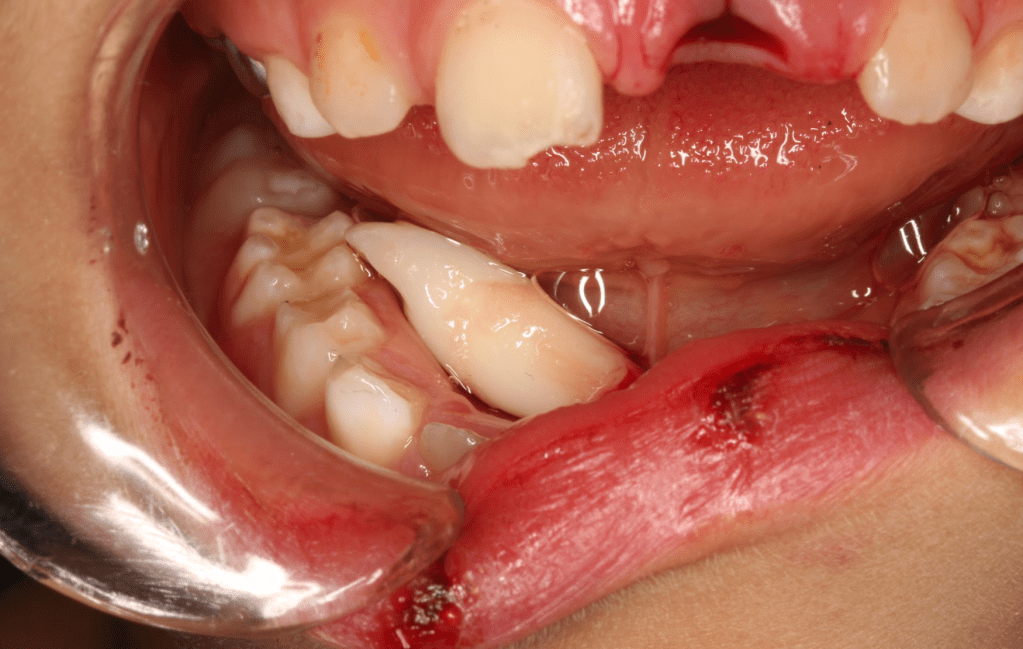

Avulsión incisivo central

Fractura con exposición pulgar

Extrusión quirúrgica